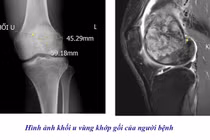

Chủ quan đau âm ỉ khớp gối, người đàn ông phát hiện u tế bào khổng lồ

Nếu không được phát hiện sớm, u xương khớp có thể phát triển, xâm lấn cấu trúc xung quanh, gây đau dữ dội, biến dạng khớp và khó khăn trong điều trị.